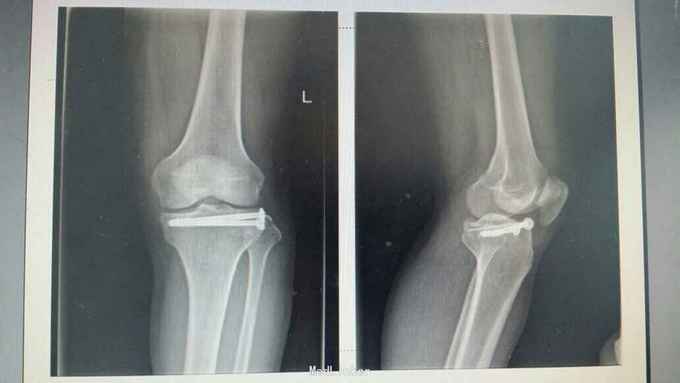

胫骨外侧平台骨折塌陷2型,关节镜下辅助骨折复位内固定术

微创手术适用于2型骨折,创伤小,恢复快,术后膝关节并发症小,患者痛苦明显减轻